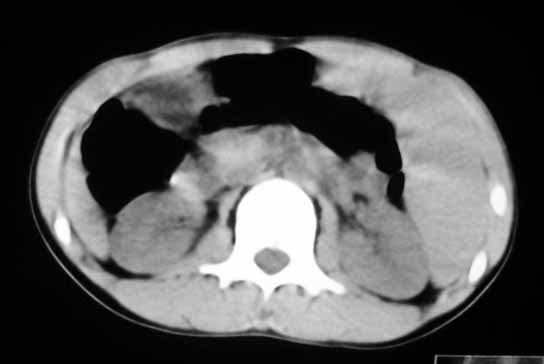

以下是引用zhangzhongshou在2007-5-22 21:04:00的发言:[br]1、脾肿大[br]2、脾脏低密度影,血管瘤?脾梗塞不能除外,建议增强扫描。

以下是引用dyqct在2007-5-22 20:45:00的发言:[br]巨脾,可疑梗塞,建议增强、查血象进一步检查

以下是引用liuyue在2007-5-23 7:57:00的发言:[br]腹主动脉周多个肿大淋巴结,脾大伴三角形低密度影,肠腔积气,考虑:1淋巴瘤2脾大伴梗塞3肠腔积气(肿大淋巴结压迫所致)